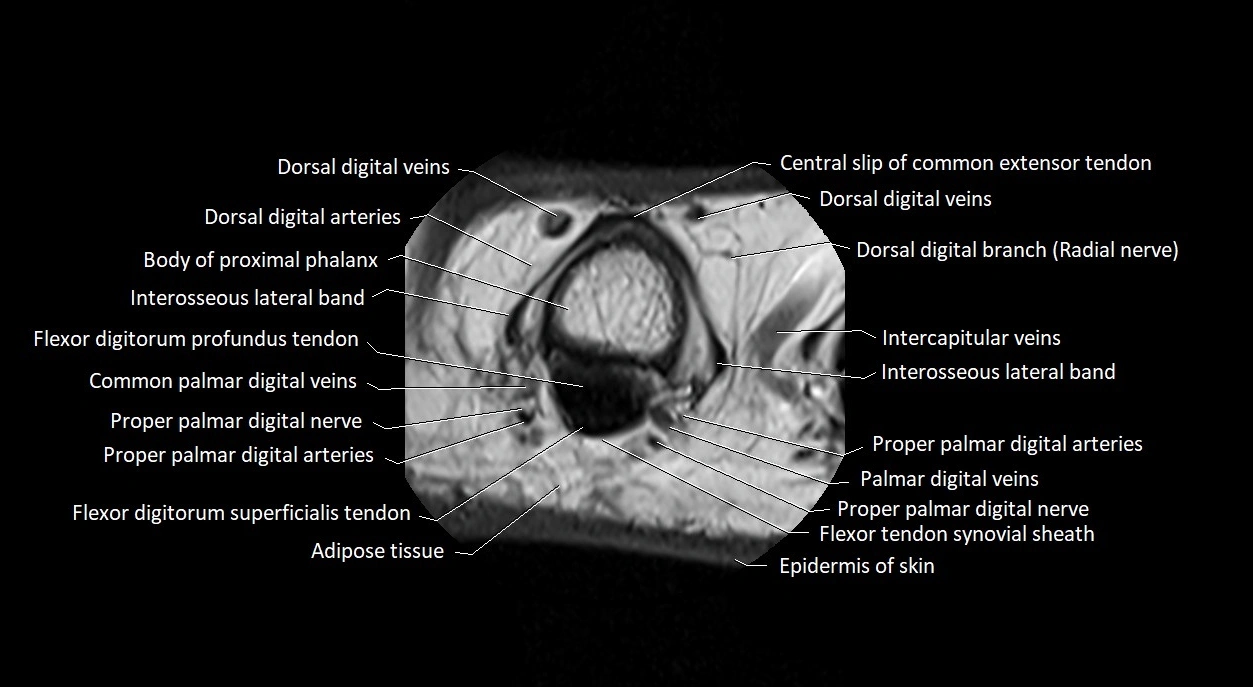

MRI images

image